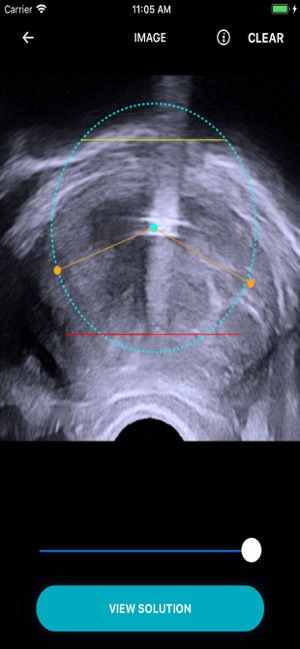

Aqublation therapy for the treatment of lower urinary tract symptom due to BPH: Angle and Contour planning steps practice.